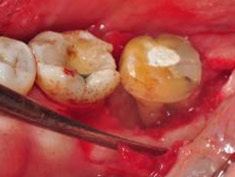

D圖為牙齦翻瓣清創後之頰側觀,#37其近心側有一寬且深,深達9毫米,型態為三壁之骨內缺損(three walls intrabony defect),頰側之根叉並無侵犯。

E圖為牙齦翻瓣清創後之舌側觀,其近心側繞舌側有一寬且深,深達5毫米,型態為合併雙壁、三壁之骨內缺損(combined two-three walls intrabony defect),舌側之根叉侵犯為1毫米。